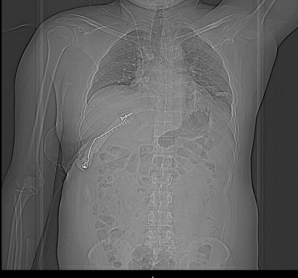

31 cases of fibromatosis were found in our database, which has data on over 10,000 patients, including those with benign bone tumours. Of these patients, 4 had desmoplastic fibroma of the bone, meaning that the incidence of fibromatosis in our population was 0.04%. Out of which three (75%) were men and one (25%) was a woman. The average age was 29.25 years (range: 21–35 years old). The skeletal distribution was one scapula, two pelvises, and one chest wall- rib. Fig-1.

Figure 1,2,3,4,5,6

Case 1- 21 year old male who presented with pain and swelling over the left scapular area , was diagnosed with left scapula fibromatosis underwent wide local excision of tumour in 2014 after clinico-radiological evaluation and post-op histopathology confirmed to be Intra-osseous fibromatosis, after 6 years patient presented with pain and local swelling and upon evaluation with X-ray Fig-2  and MRI which showed Hyper-intense lesion on T2 sequence measuring 11.2x14.5x11.3cm with destruction of scapula body and spine with soft tissue deep to the deltoid - coronal and axial images Fig-3 and Biopsy confirmed to have local recurrence and considering chance of recurrence again patient underwent Type 3 intra-articular scapulectomy with gross histopathology image and microscopic image Fig-4. And currently on 3 year follow up and no local recurrence.

Case 2- 35 year old male who presented with a chest wall swelling and pain upon evaluation MRI was suggestive of a T1 intermediate and  T2/STIR intermediate to Hyper-intense lesion  from the Right 9 rib with extra-osseous soft-tissue component – coronal and axial images Fig-5 and histo-pathologically was found to have introsseous fibromatosis of the 9th rib. Following multidisciplinary team discussion and keeping in mind about the extra-osseous component  and complex location of tumor patient was planned for a wide local excision of the tumor. The tumor was removed En-bloc along with part of the 10th rib because of the close proximity to 10th rib. Reconstruction was done using screws fixed to the cut ends of the bone and tagged with sternal wire and poly-methyl methacrylate mould was used to reconstruct the rib cage and augmented with mesh Post-op reconstruction X-ray Fig-6. Following the surgery on 2 year follow-up patient is disease free and doing well.